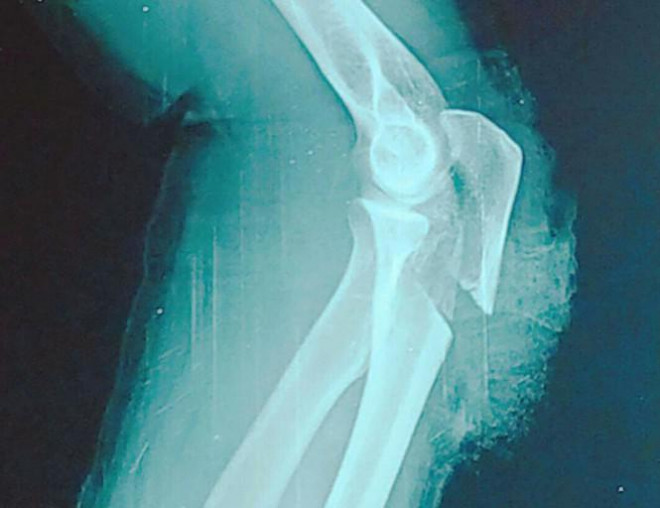

Cánh tay bị đứt gần lìa

Sau khi ra tay, hung thủ nhanh chóng rời đi. Hai nạn nhân bị thương nặng phải nhập viện cấp cứu, trong đó một người bị đứt gần lìa cánh tay.